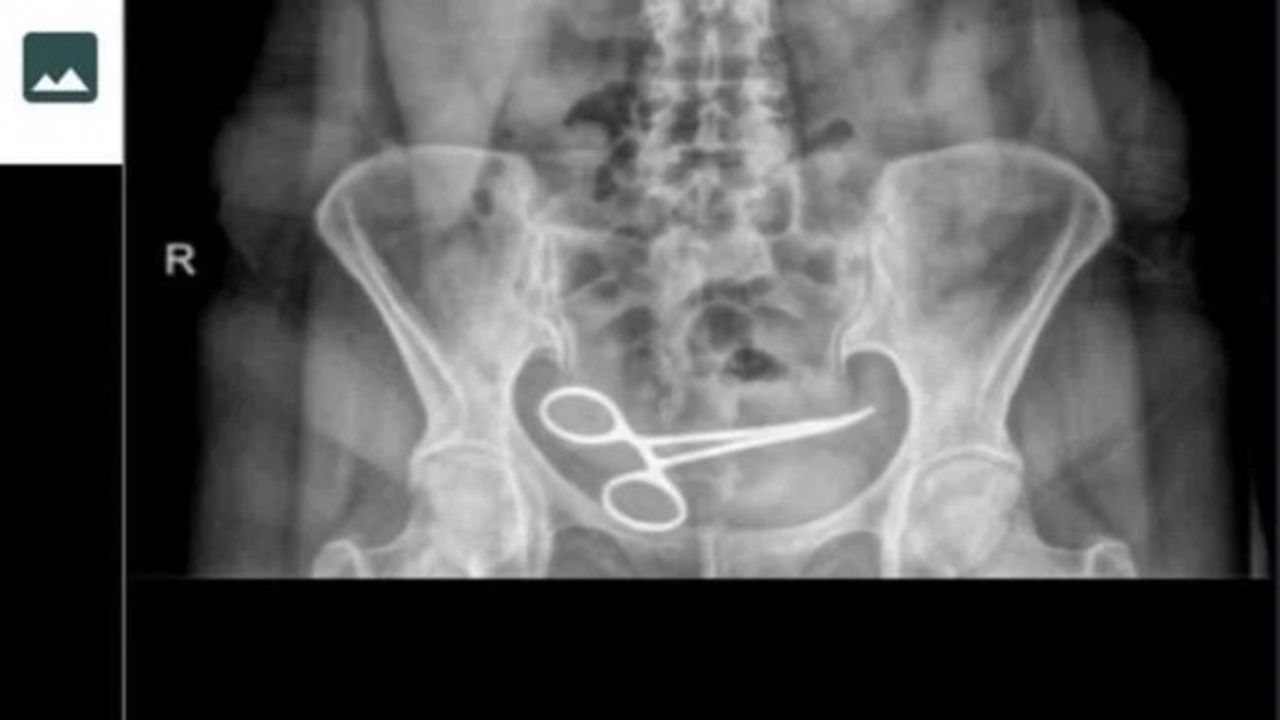

Ankara'da Şadiye Boyun, 28 Aralık 2021 tarihinde Pursaklar ilçesinde, özel hastanede bir kadın hastalığı nedeni ile ameliyat oldu. Ameliyattan 8 ay sonra karın ağrısı şikayeti görülen Boyun, ambulans ile Pursaklar Devlet Hastanesi'ne kaldırıldı. Burada çekilen röntgende Boyun'un ince bağırsağına takılı 12 santim boyunda makas olduğu görüldü. Ardından iddiaya göre, ameliyatın gerçekleştirdiği özel hastaneye haber verildi. Özel hastaneden görevliler geldi.

Görevliler tarafından tekrar özel hastaneye götürülen Boyun'un röntgeni çekildi. Bunun üzerine oğlu Fatih Boyun, durumdan şüphelenerek e-Nabız uygulamasından röntgen sonuçlarına baktı ve annesini Gülhane Eğitim ve Araştırma Hastanesi'ne sevk ettirdi. Şadiye Boyun'un karnındaki makas ameliyatla alındı. Boyun, avukatı aracığıyla, ameliyatı gerçekleştiren doktor ve hastane hakkında suç duyurusunda bulundu.